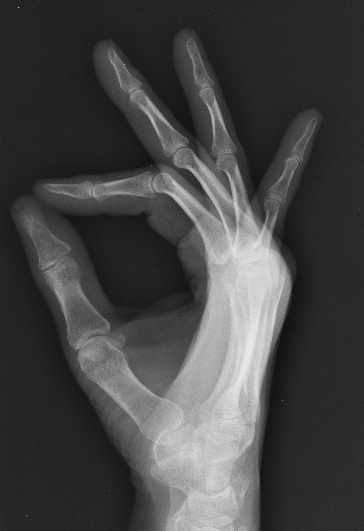

Protect Your Money-makers

Xray 1

If you spend tons of time clicking away at a keyboard, mouse or track pad and your wrist is not at an ergonomically agreeable angle, you may have experienced the tingling and numbness of carpel tunnel syndrome (CTS). Try raising your chair, resting your feet on a box (necessary with higher seat), and buying a mouse pad with an attached wrist support. Not enough? Become ambidextrous! Training my non-dominant hand to perform simple tasks, including most of my non-artistic clicking, helped me out a lot.